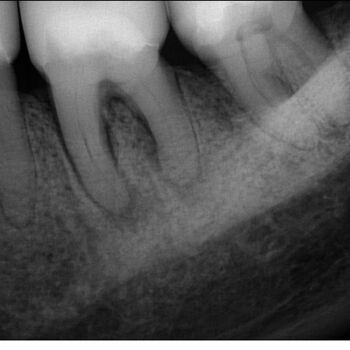

Fall 3: Obliterierte Kanäle

Ausgangssituation

Kontrolle nach Wurzelfüllung